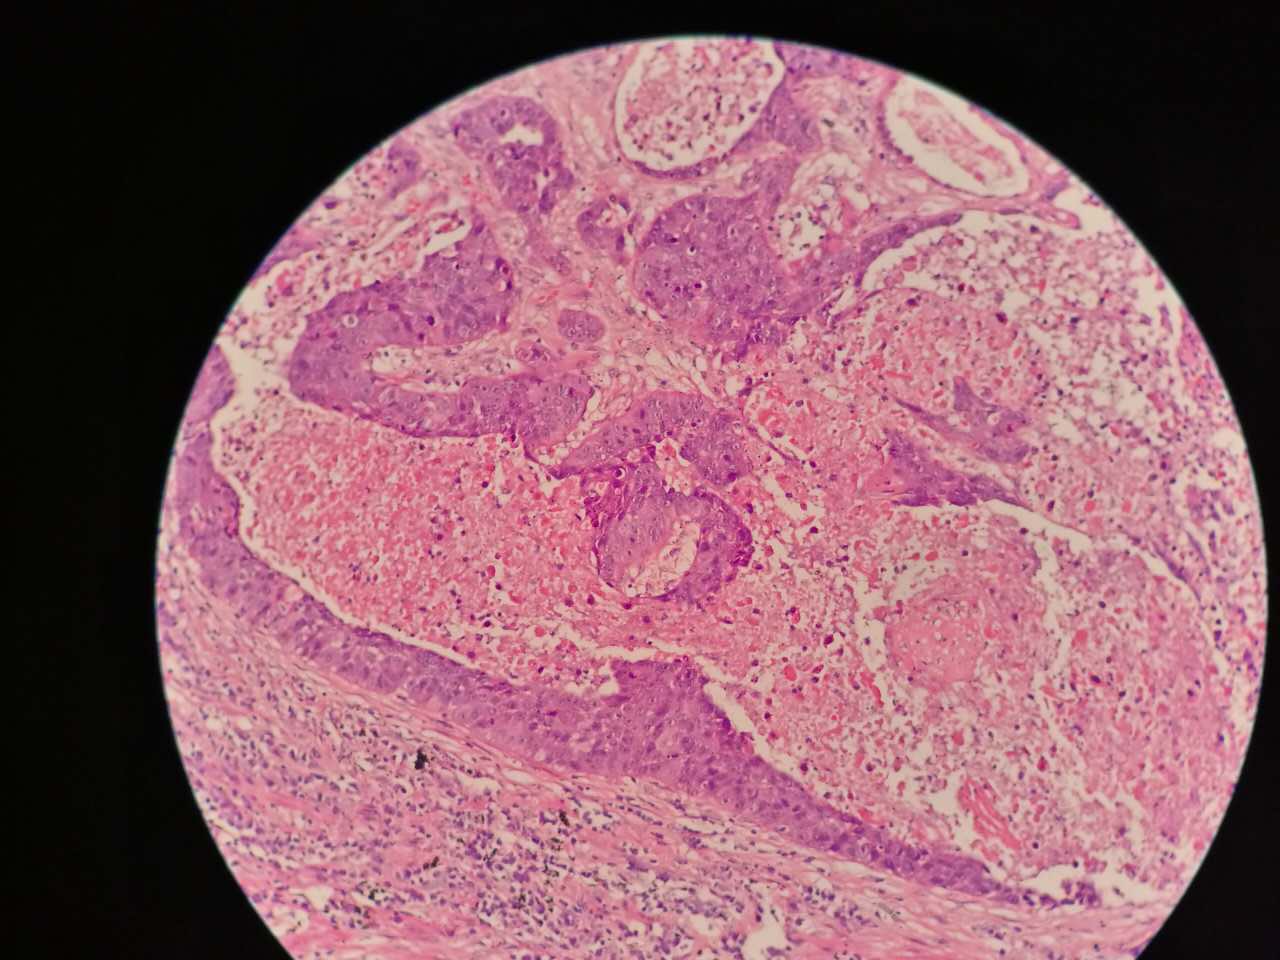

左手边有一点鳞癌,右手边有正常肺泡组织,中间有坏死物,这是为什么呢?

坏死物质渗出。

并且可以有吞噬,坏死物里常有血液成分

剖面多呈黄色

肿瘤周围不应是缺血,坏死一般在巢团内

这是一般的鳞癌,坏死大

一侧常有突起,也就是壁结节。

壁结节不必等到空洞形成才判断,有坏死区就可以在增强片上判断有无壁结节

这个中央那块也算是小型的壁结节,肿瘤组织突入坏死区。或者说,这块肿瘤组织没坏死。